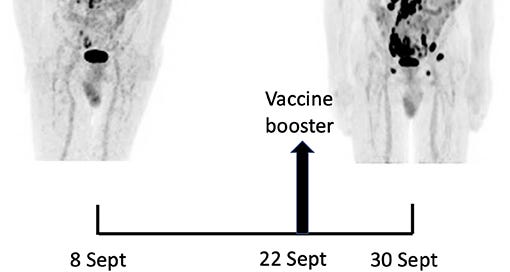

Related to the above research, we have from 2021: “Rapid Progression of Angioimmunoblastic T Cell Lymphoma Following BNT162b2 mRNA Vaccine Booster Shot: A Case Report”18:

A 66-year-old man with no significant medical history except for hypertension, hypercholesterolemia and type 2 diabetes presented on September 1, 2021 with cervical lymphadenopathies that became recently apparent during a flu-like syndrome. The two doses of BNT162b2 mRNA vaccine had been administered, respectively, 5 and 6 months earlier in the left deltoid. Besides moderate asthenia, he did not report any constitutional symptom. Blood examination indicated a mild inflammatory syndrome, without anemia or white blood cell changes; Lymphocytes immunophenotyping was unremarkable. Protein electrophoresis and immunoglobulin levels were normal and Coombs test was negative.

A 18F-FDG PET/CT revealed multiple voluminous hypermetabolic lymphadenopathies above and below the diaphragm as well as several extra-nodal hypermetabolic lesions (Figure 1, left panel). Considering a presumptive diagnosis of stage IV lymphoma, a left cervical lymph node biopsy was performed. Pathological examination revealed residual atrophic germinal centers, surrounded by an expanded paracortical area composed of an atypical T-cell infiltrate with clear cell morphology, expressing TFH cell markers (CD3, CD4, PD1, ICOS, BCL6, CXCL13) and a loss of CD7. The paracortical area contained an increased number of high-endothelial venules, supported by an increased number of follicular dendritic cell networks, with some foci of EBV+ B-cell immunoblastic proliferation in the background (Figure 2). These features highly suggested a diagnosis of AngioImmunoblastic T cell Lymphoma (AITL), pattern 2. Next generation sequencing (NGS) performed on the biopsy specimen identified the RHOA G17V mutation characteristic of AITL (5) together with the DNMT3A, IDH2 and TET2 mutations. A TCR-gamma gene rearrangement confirmed a clonal T cell proliferation. Altogether, these findings unambiguously established the diagnosis of AITL. A bone marrow biopsy did not reveal neither morphological nor phenotypic abnormalities, but NGS revealed DMNT3A and TET2 mutations in bone marrow cells with allele frequencies of 41% and 36%, respectively.

Fourteen days after the PET/CT, a booster dose of the BNT162b2 mRNA vaccine was administered in the right deltoid in preparation of the first cycle of chemotherapy. Within a few days following the vaccine booster, the patient reported noticeable swelling of right cervical lymph nodes. In order to get a baseline close to the initiation of the therapy, a second 18F-FDG PET/CT was performed 8 days after the vaccine booster administration, i.e. 22 days after the first one.

This wasn’t just stimulating the TFH cells, it was tumorigenic in action:

It demonstrated a clear increase in number, size and metabolic activity of pre-existing lymphadenopathies at the supra- and sub-diaphragmatic level. Furthermore, new hypermetabolic lymphadenopathies and new hypermetabolic sites had developed since the first examination, in several different locations (Figure 1, right panel).

Total lesion glycolysis (TLG), which measures metabolic activity, was used to monitor changes in lymph node activities:

As compared with the initial test, there was a marked 5.3-fold increase in whole-body TLG, with the increase in the post-booster test being twice higher in the right axillary region than in the left one. In parallel, a mild increase in blood levels of ferritin, C-reactive protein and LDH were noted.

To the best of our knowledge, this is the first observation suggesting that administration of a SARS-CoV-2 vaccine might induce AITL progression. Several arguments support this possibility. First, the dramatic speed and magnitude of the progression manifested on two 18F-FDG PET-CT performed 22 days apart. Such a rapid evolution would be highly unexpected in the natural course in the disease. Since mRNA vaccination is known to induce enlargement and hypermetabolic activity of draining lymph nodes, it is reasonable to postulate that it was the trigger of the changes observed. Indeed, the increase in size and metabolic activity was higher in axillary lymph nodes draining the site of vaccine injection as compared to their contralateral counterparts. However, pre-existing lymphomatous nodes were also clearly enhanced as compared to the first test. Moreover, new hypermetabolic lesions most likely of lymphomatous nature clearly appeared at distance of the injection site.